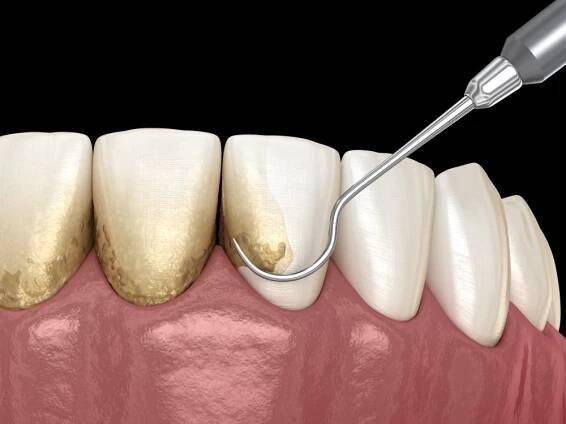

Parodontóza, parodontitida nebo také hovorově paradentóza je zánět takzvaného závěsného aparátu zubu. Předcházet a v počátečních fázích ji i léčit lze dobrou zubní hygienou. Jinak může skončit až ztrátou chrupu.

Parodontitida (parodontóza, paradentóza, paradontóza) je zánětlivé onemocnění závěsného aparátu zubů čili parodontu (lat. parodontium).

Paradontóza je zánětlivé onemocnění zubů a přiléhající tkáně. Někdy může zasahovat až do přilehlých kostí.

Ty jsou obsaženy v nahromaděném mikrobiálním povlaku na povrchu zubů. Bakterie uvolňují jedovaté látky – toxiny, které poškozují okolní tkáně a způsobují zánět.

Parodontitidu způsobuje zanedbaná ústní hygiena. Je velkým strašákem zubů, ale i jejich majitelů. Jde o zánětlivé onemocnění dásní i okolního aparátu, na kterém jsou zuby zavěšeny.